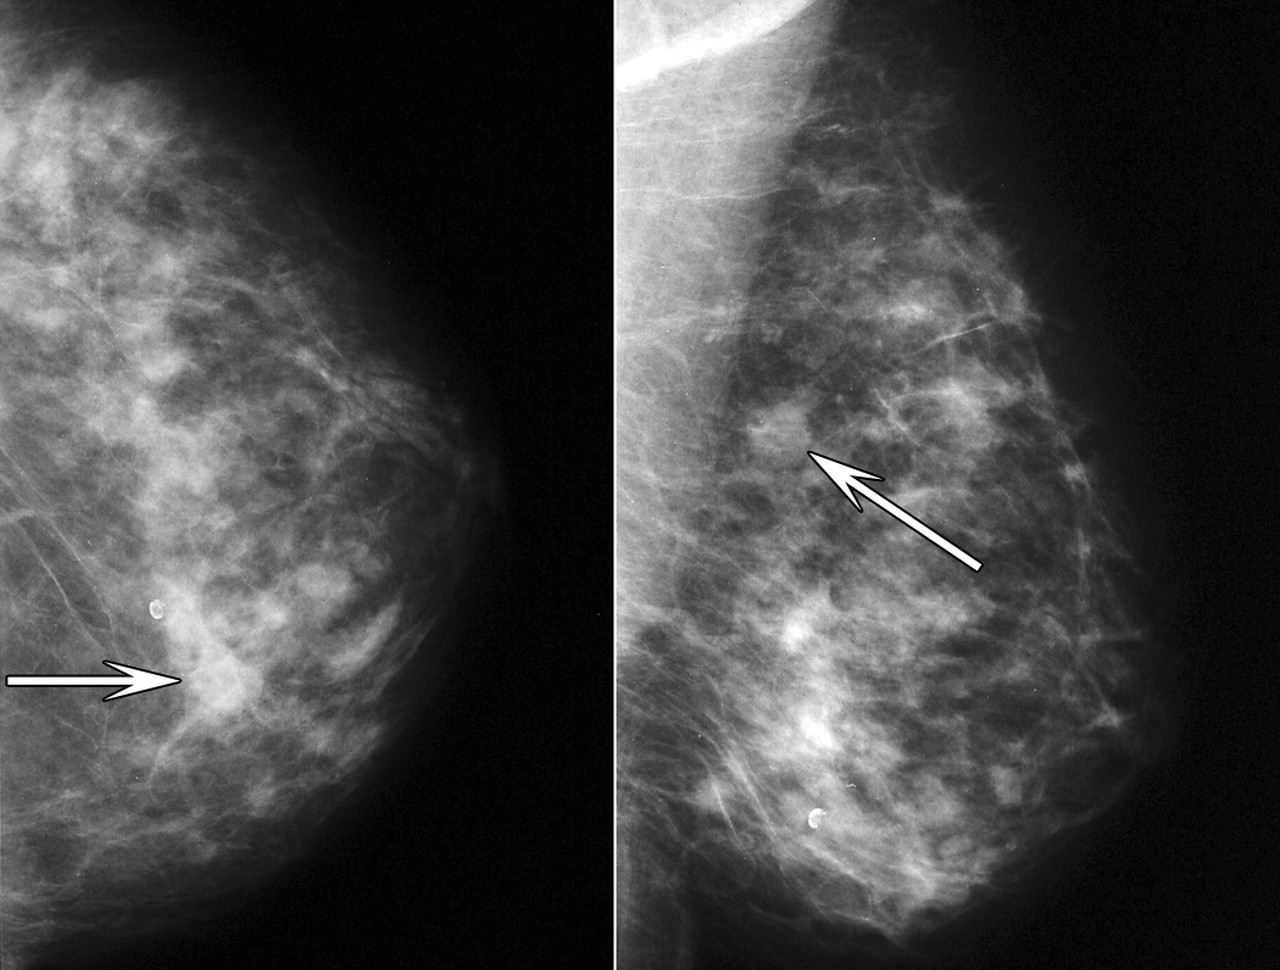

유방 촬영술(Mammography)

단순 X선을 이용하는 것으로, 모든 유방 질환을 발견하고 진단하는데 가장 기본적인 검사다.

병변의 유무를 쉽게 알 수 있을 뿐만 아니라 만져지지 않는 석회화 병변을 발견하는 데에도 가장 효과적이다.

매년 혹은 1~2년 간격의 정기적인 유방촬영술만으로도 유방암을 조기발견할 가능성이 높다.

유방촬영으로 관찰되는 석회화 소견은 매우 다양해서 유방암이 아닌 경우가 많지만, 0기 유방암이나 초기의 유방암은 혹을 만들지 않고 석회화만 보이는 경우가 있으므로 반드시 유방전문의와 상의해야 한다.

유방암이 의심되는 석회화 병변의 경우, 유방초음파나 MRI(유방자기공명영상)와 같ㅇ느 정밀검사를 필요로 하며 조직검사를 시행하는 것이 원칙이다.